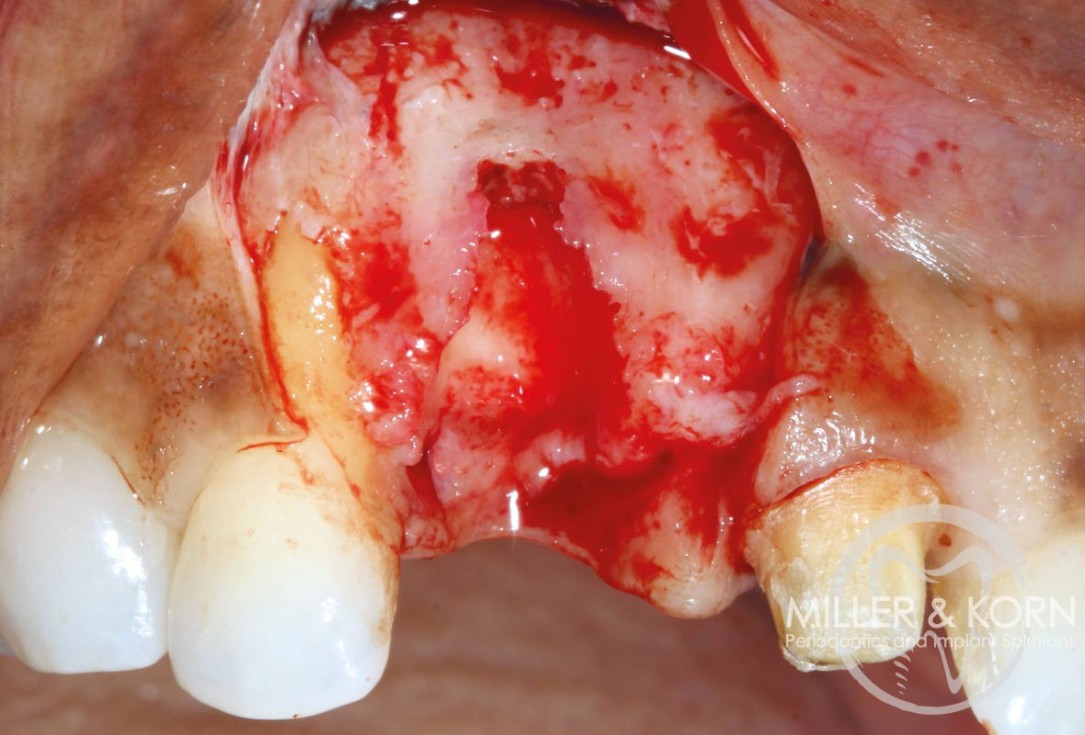

4/22 - Full thickness flap elevation with vertical releasing incisions. Note, significant apical and buccal bone resorption after raising the flapImmediate implant placement and regeneration of ridge using an allograft bone ring and Jason® membrane - Drs. Miller and Korn